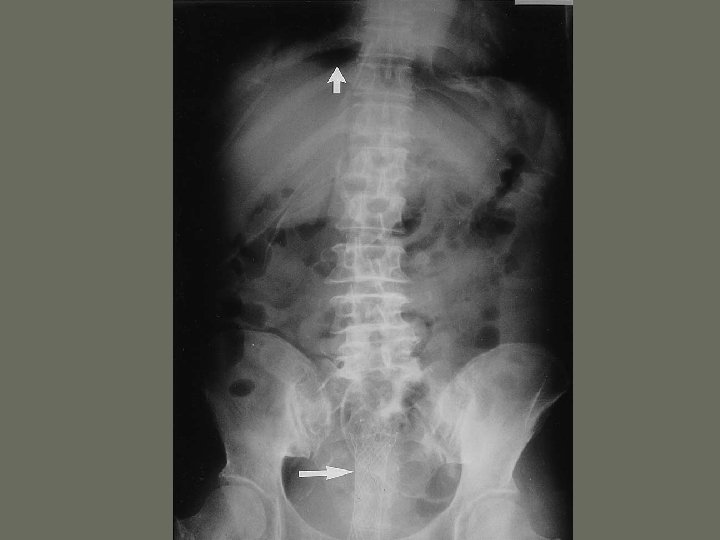

Interventional Procedures 7. Inferior vena cava filter • catches an _____ before is reaches the small vessels in the heart • prevents a pulmonary embolus